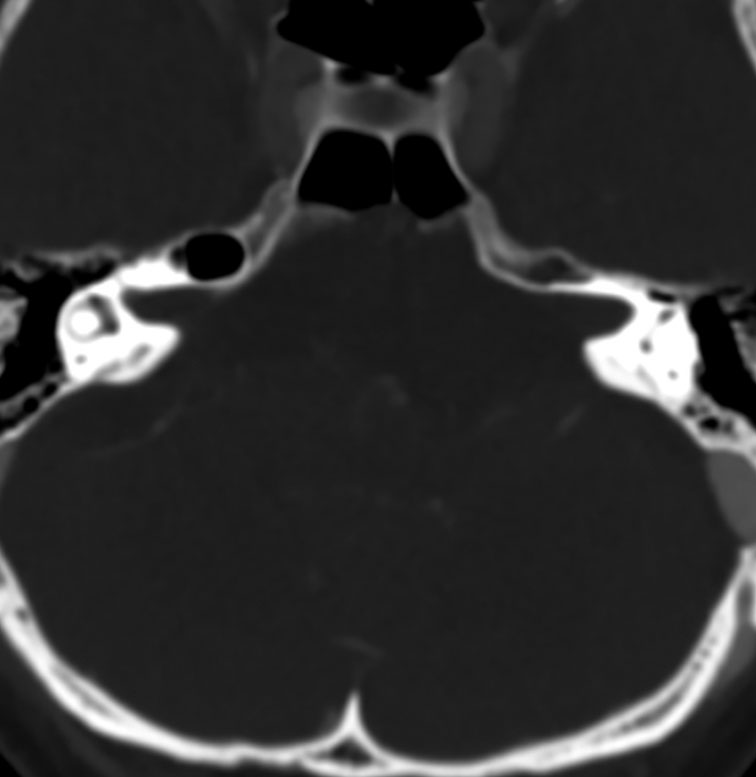

骨をみているCTです。鞍背からsphenooccipital synchondrosisまでの斜台骨皮質が失われています。かなり特徴的な所見です。